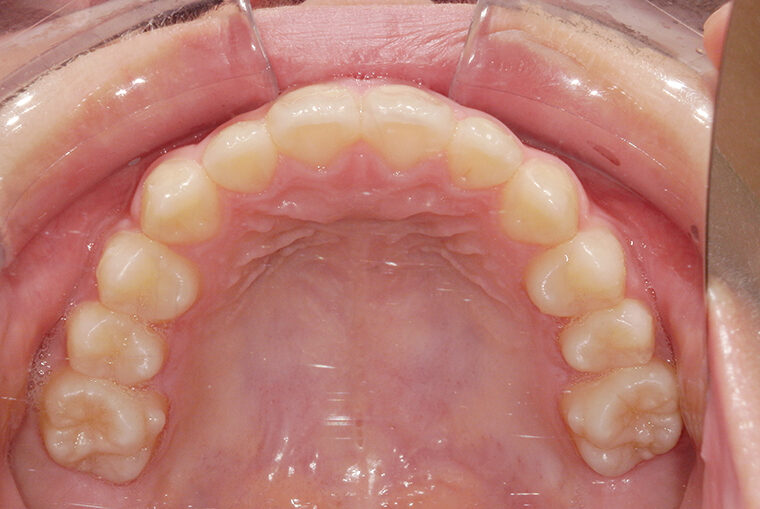

Case Study9歳女性ガタガタな歯のマウスピース矯正-矯正期間1年6ヶ月